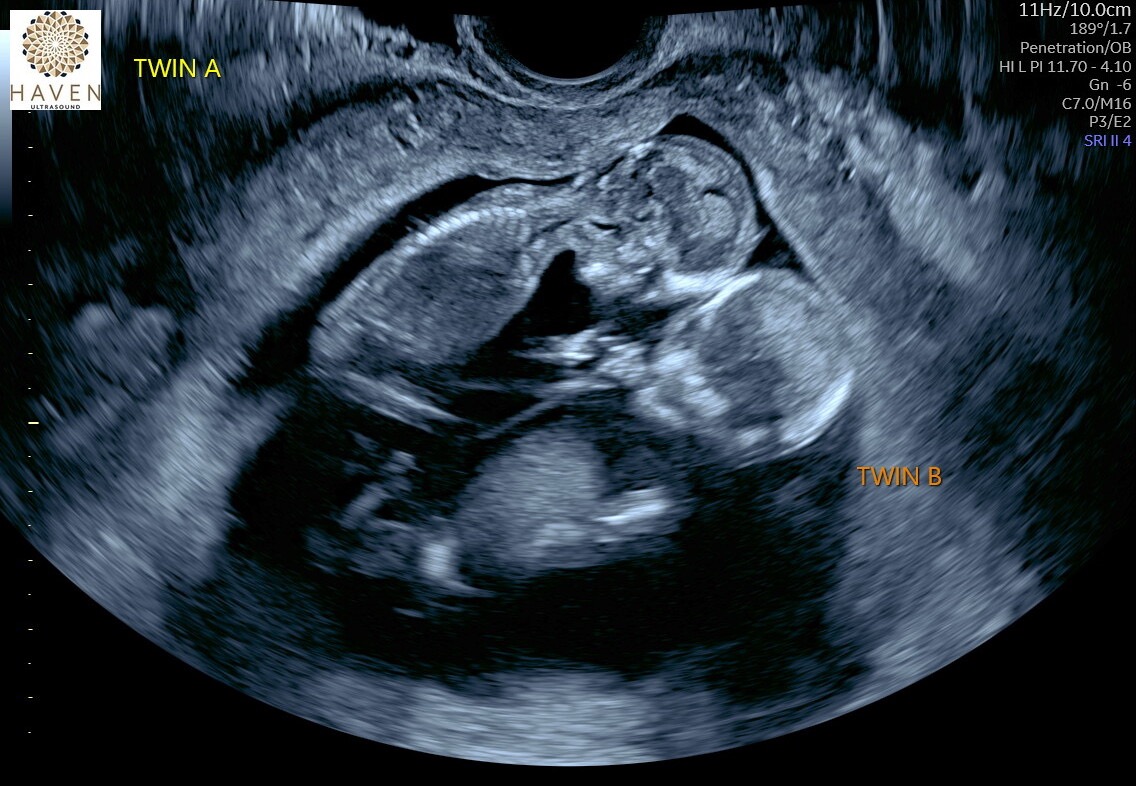

We are shattered to share that our dear coworker and friend, Maxxe, has endured the most traumatic and heartbreaking experience a mother can face. At just 18 weeks pregnant, Maxxe went through the agonizing ordeal of giving birth to her identical twin boys, Quentin and Spencer, who were born sleeping.

Though Quentin and Spencer never got to breathe a breath in the out side word, they are forever loved, cherished, and remembered. Their tiny lives, though brief, will always hold a place of honor in their mother’s Maxxe’s heart.